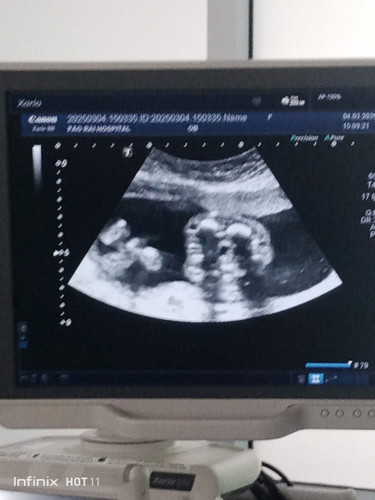

แม่ๆรู้เพศกันหรือยังคะ บ้านนี้ 20 วีค คุณหมอนัดซาวด์ ดูตั้งนานกว่าจะรู้ น้องมีแคมนิดนึงแล้วค่ะ คุณหมอก็เลยบอกว่าเป็นผู้หญิง 100% แม่ก็อยากได้ผู้หญิงนะ เพราะดูจากท้องแล้วแตกต่างจากคนแรกมากค่ะ มาคุยกันนะแม่ๆได้ผู้หญิงหรือผู้ชายกำหนดคลอดเดือนไหนคะ